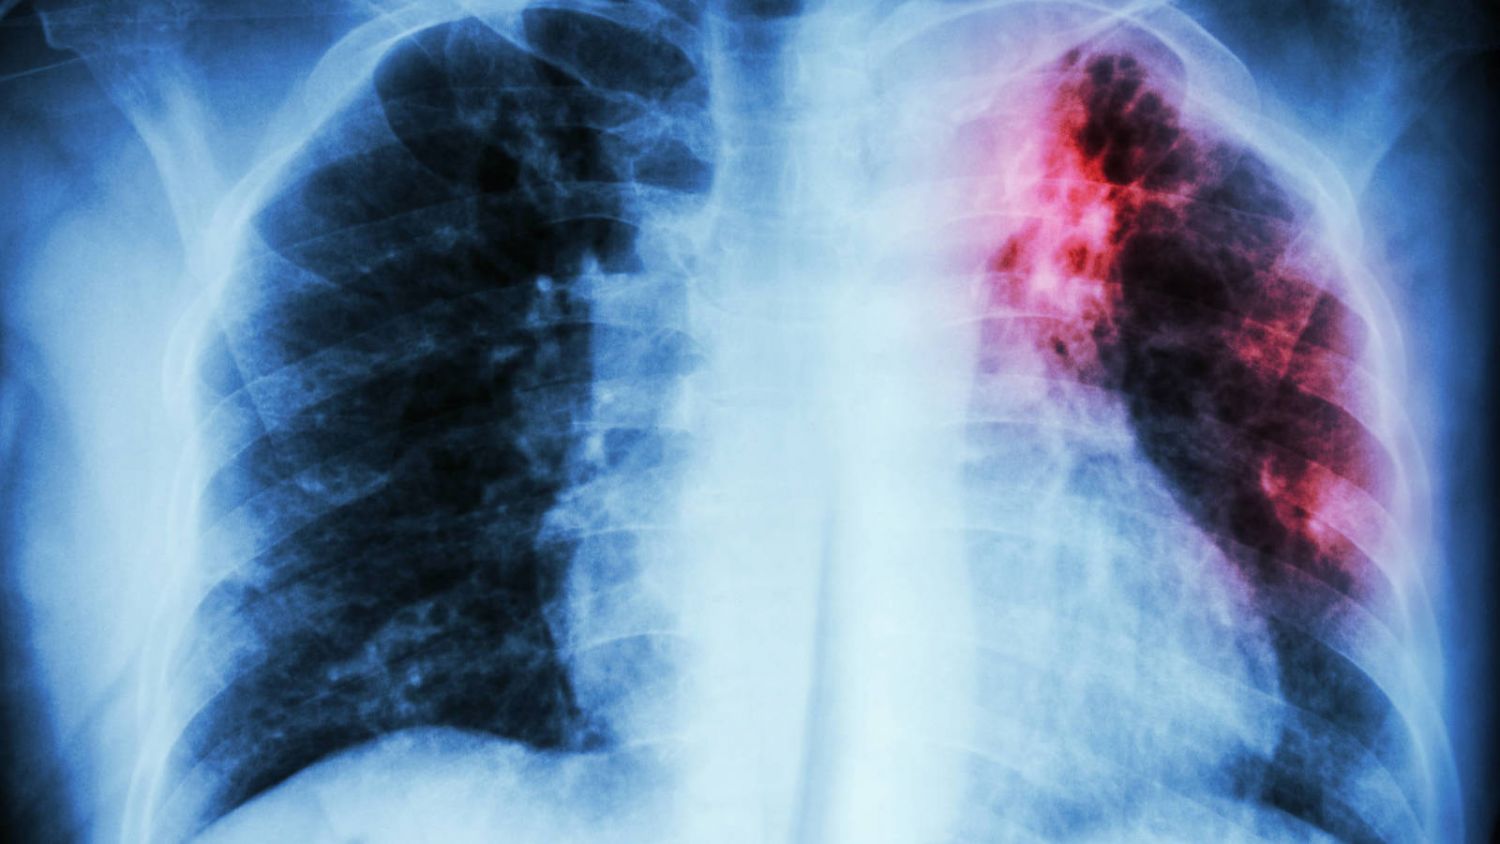

- Rayos x

- Radiografía de tórax y tomografía computarizada.